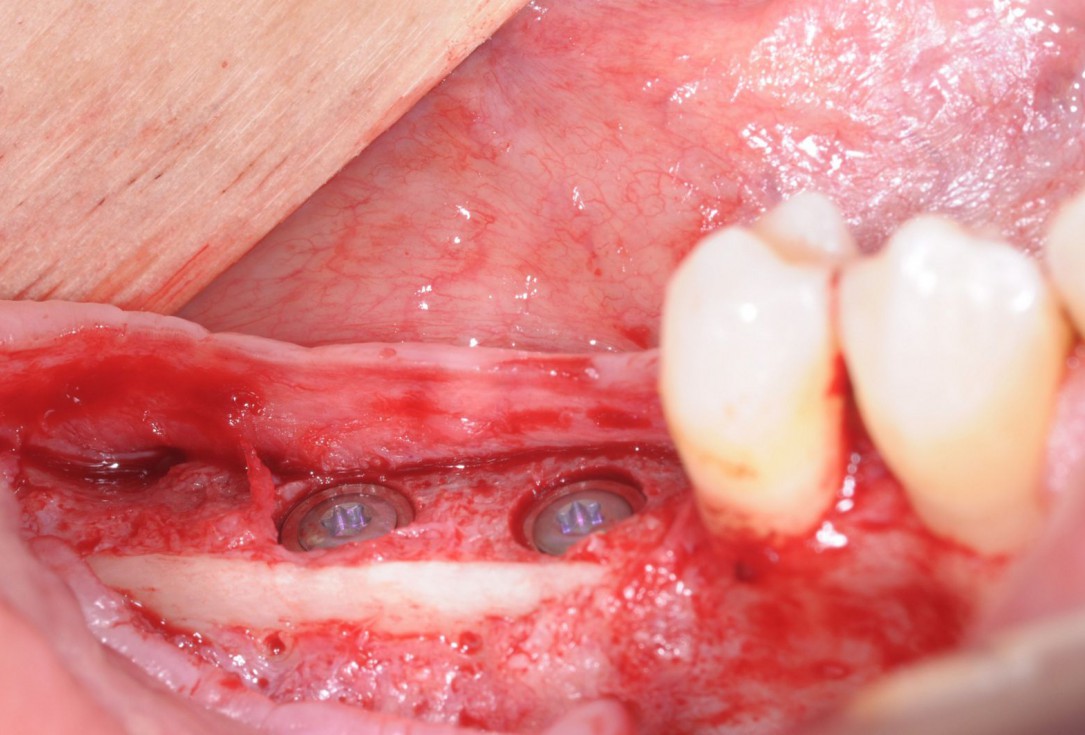

19/28 - Placement of implant cover screws in the fully submerged dental implantsThree-dimensional augmentation with maxgraft® cortico - Dr. R. Würdinger

20/28 - Occlusal view of the implants with cover screwsThree-dimensional augmentation with maxgraft® cortico - Dr. R. Würdinger